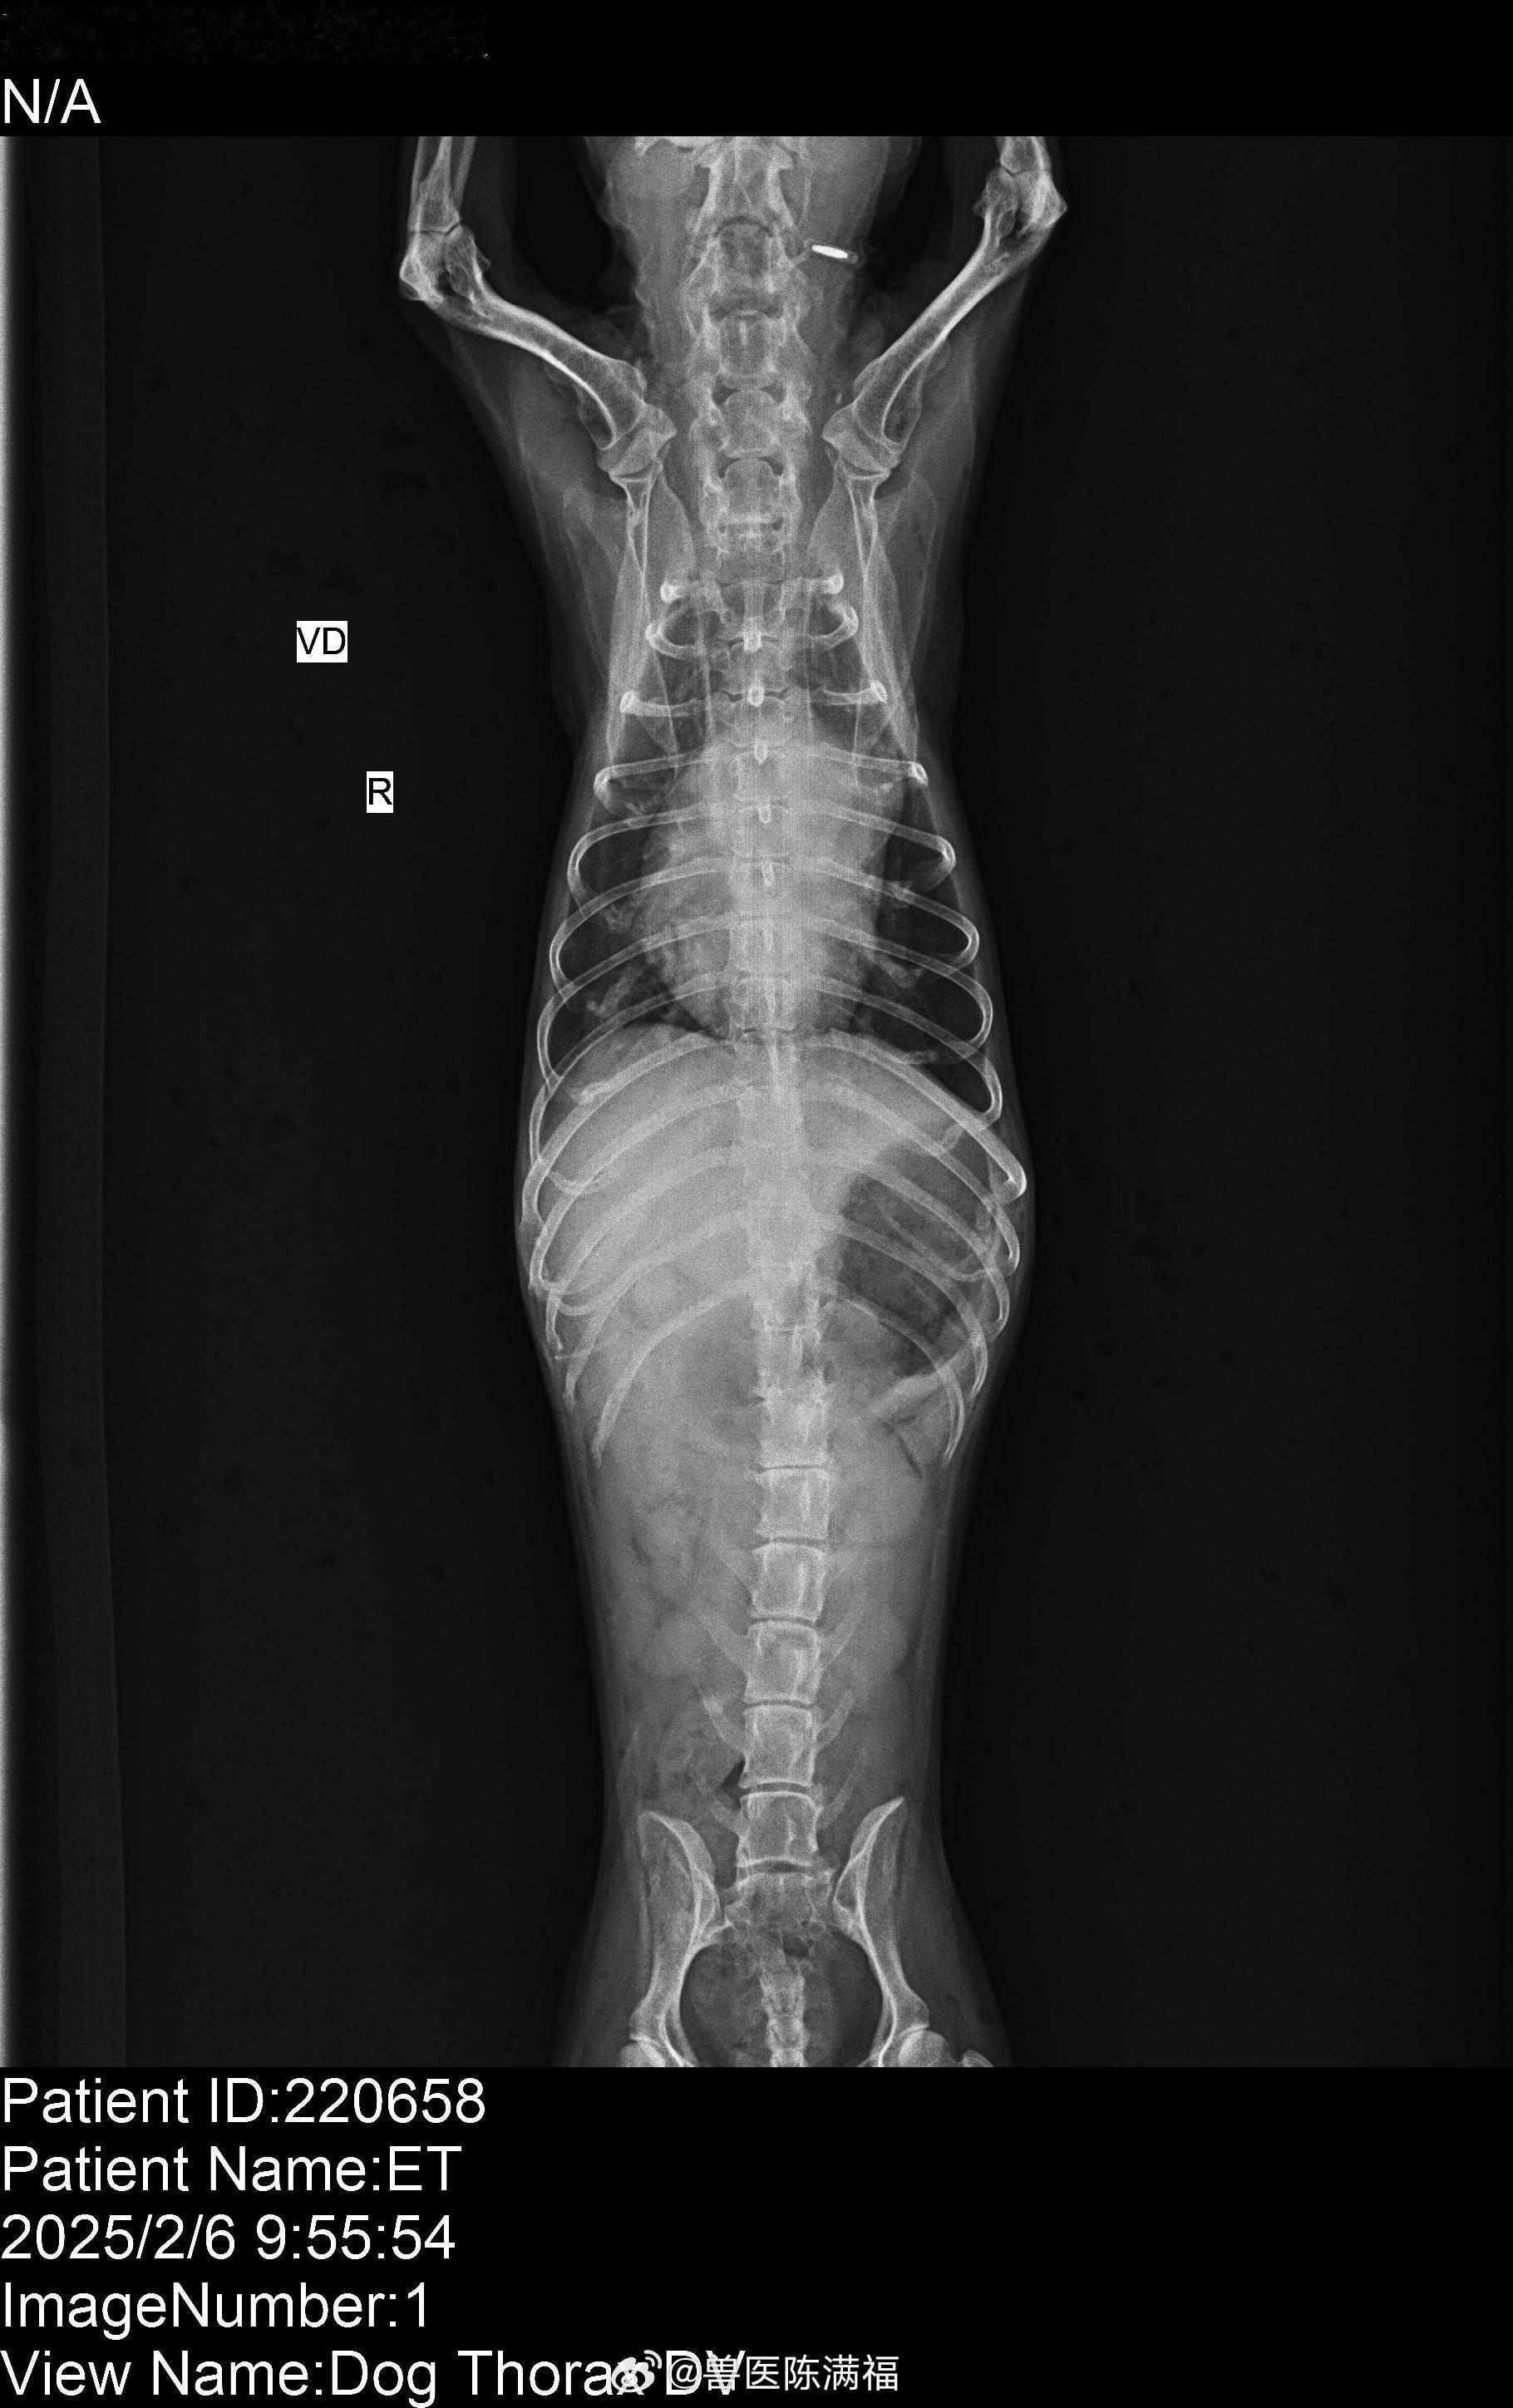

肺水肿好了很多继续加油。苏州卓越宠物医院最近心脏病肺水肿很多

肺水肿好了很多

继续加油。

苏州卓越宠物医院

最近心脏病肺水肿很多